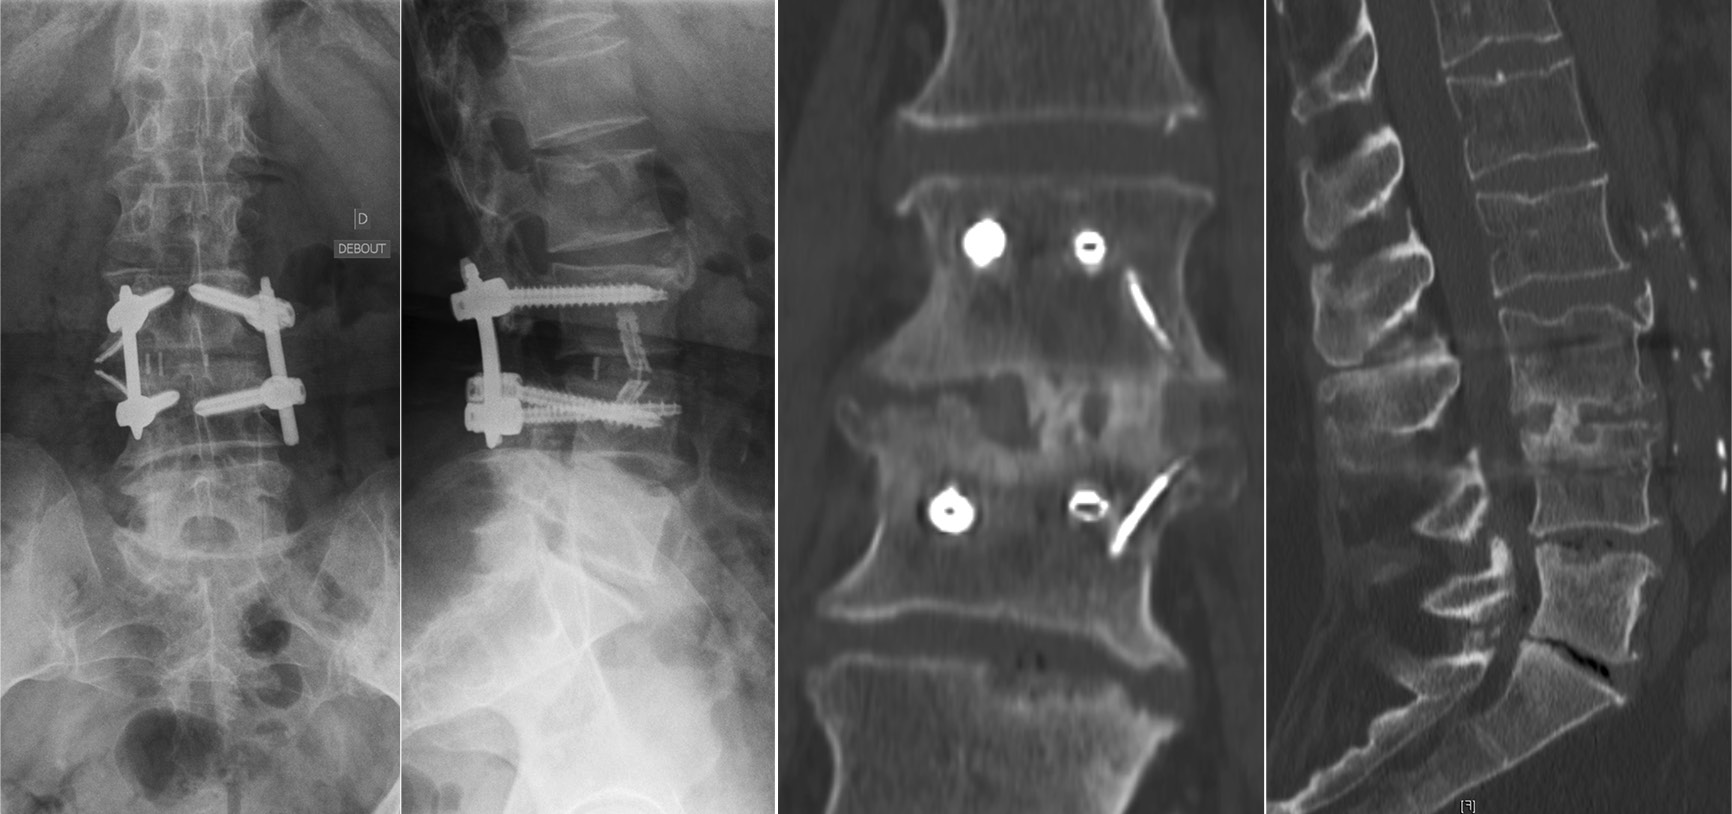

腰椎L3-4椎间融合联合后路经皮椎弓根钉内固定。1年随访时CT显示椎间骨性融合

不融合与内固定棒断裂

如果术后患者在随访过程中出现疼痛,并且X光片显示内固定棒断裂,则应高度怀疑脊柱出现不愈合的情况。在判断节段不融合时,应不断强调内固定棒在单一节段上发生断裂,并不代表仅存在该节段的脊柱不融合,应警惕多节段不融合的风险。所有脊柱节段均应在影像学上进行仔细检查,并在术中进行探查,以避免多次的翻修手术。文中,作者还特别强调了Ponte截骨在应用此类患者时的注意事项。Ponte截骨术在当通过有力的加压对节段性后凸畸形进行矫正时,前方骨赘可能会出现破裂,导致前方狭窄的椎间隙张开。此时,必须通过前路支撑与植骨来稳定这些节段,以防止术后矫正丢失与不融合情况的发生。如果已经发生,则建议使用OLIF进行前路的支撑融合。

脊柱不融合内固定棒断裂

Ponte截骨使狭窄的间隙在前方张开,后期可能缺乏良好的前柱支撑出现不融合

作者在文中描述避免不融合与内固定棒断裂的方法时说明,如果固定节段包括骶骨与骨盆时,仅仅依赖后方的融合而没有前柱的支撑可能还是不够的。作者仍然建议在前柱采用ALIF或TLIF技术避免不融合或再手术的发生。同时,今年来在针对内固定棒断裂的问题时,双棒技术的应用已表现出良好的临床结果,在文献报道中能够降低不愈合的风险。增加卫星棒的目的在于增加两个额外的内固定棒来加强固定并分担一部分应力,降低单一内固定棒所承受的应力。

双棒技术的应用